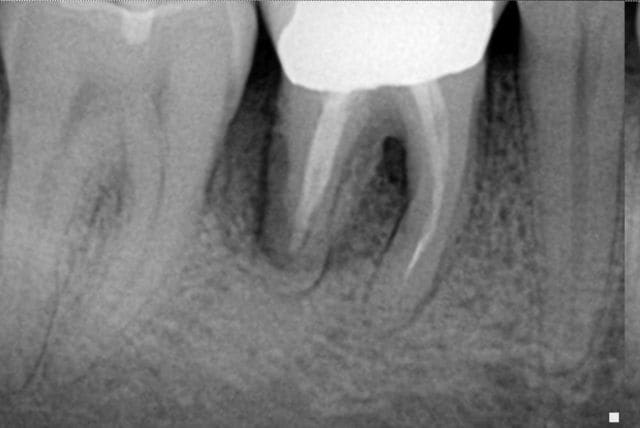

En mars 2011 abcès paro sur 46: antibiotique puis assainissement des poches, irrigation et mise en place de Paroclean.

Mais la semaine dernière : à nouveau abcès (voir radio)

il y a 3mm de rétraction gingivale, 4mm de poche en mésial, 6mm à la furcation et 4mm en distal (désolé pas de photo !)

T'as vu la gueule de l'obturation endo?

Peut etre que ton abcés paro est tout simplement une lésion endo-paro.

Moi je reprendrais le traitement endo en premiere intension ensuite on passe à la paro.

ça ressemble étrangement à un problème endo- paro, même si le traitement radiculaire semble correct (petit bémol l'instrument fracturé en mésial)

atteinte paro en distal en doigt de gant il me semble

atteinte de la furcation

instrument pété intracanalaire

endo douteuse

Même si l'endo n'est pas terrible, l'historique de la lésion montre que c'est purement paro (désolé je ne peux exporter les anciennes radios...)